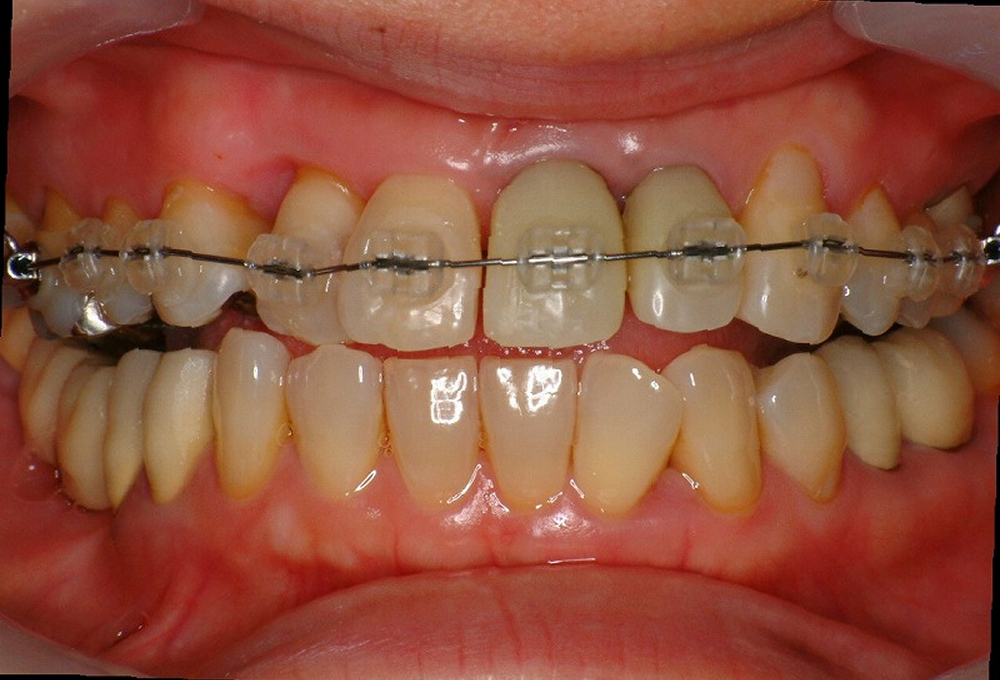

②矯正中